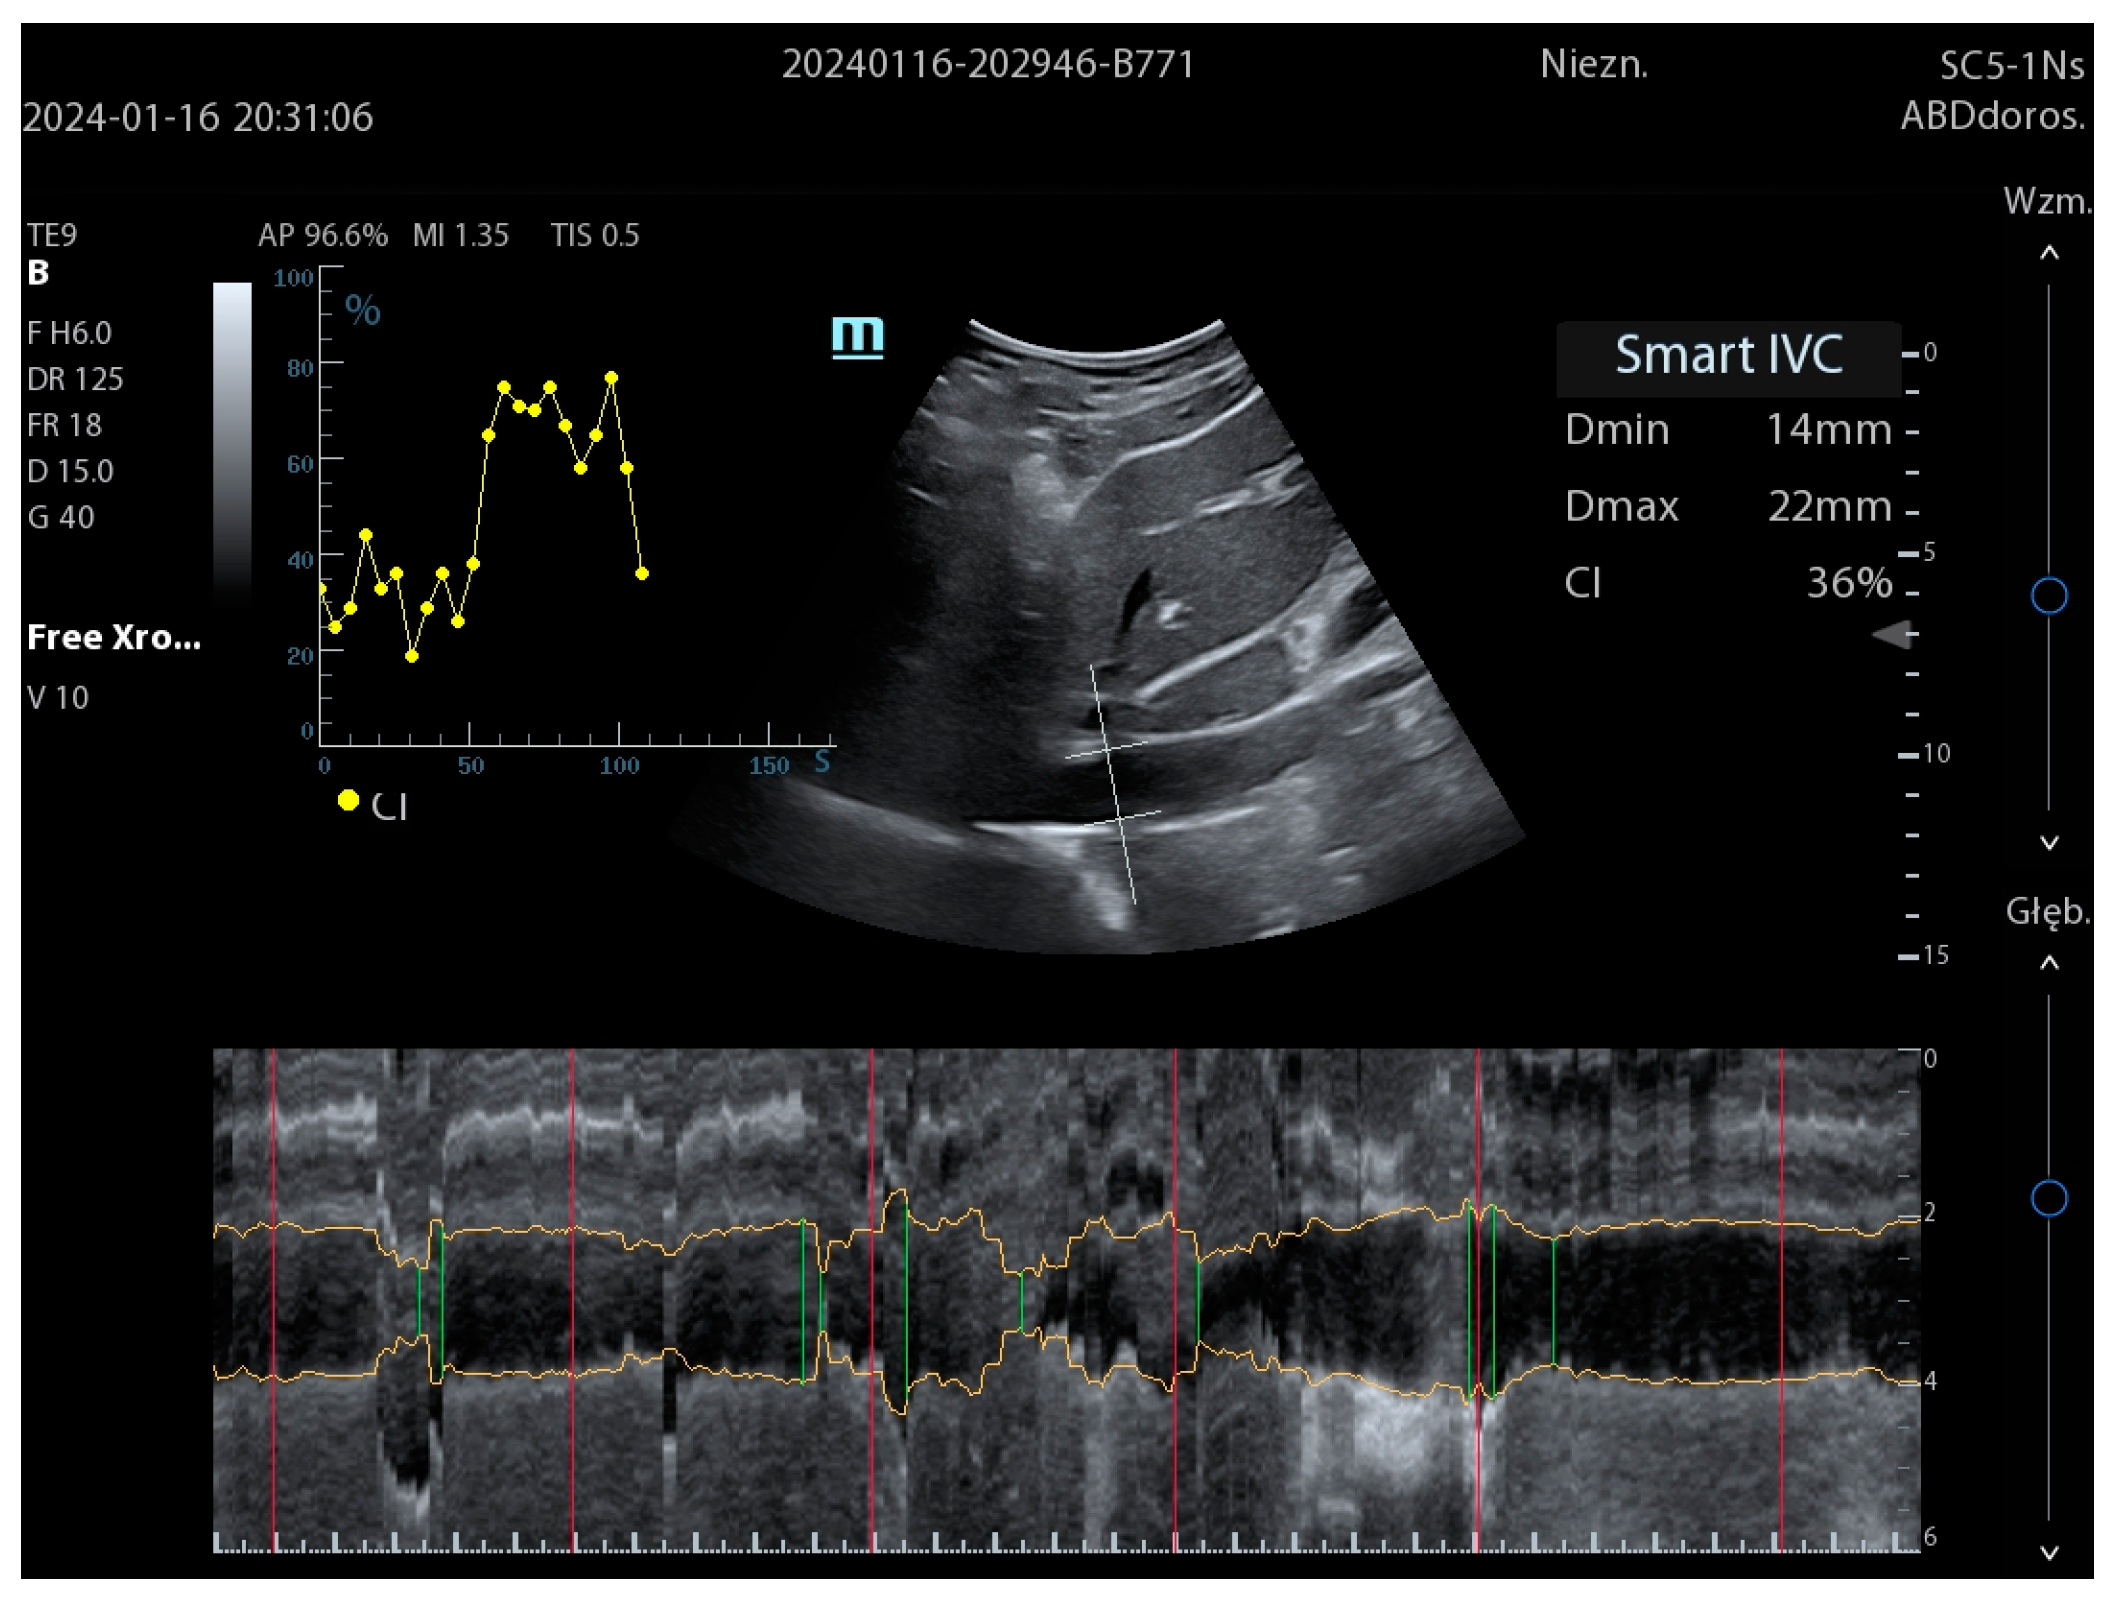

| SmartIVC | Mindray | automatic measurement of the inferior vena cava (IVC) | Internal Vena Cava examination |

| AutoIVC | GE | ||